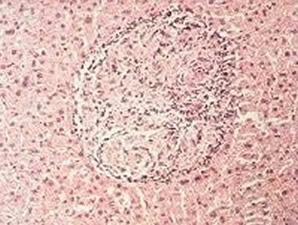

The Coccidia is also known in its initial state as an Oocysts (pronounced o'o-sists), which can easily be visualized as a little “o” inside of a big “O” as seen through the microscopic picture below. Coccidia are spread through fecal matter. Such infected fecal matter is easily passed through contact with other animals or the areas they habitate. Squirrels, birds, people’s shoes, hands, car tires and even the rain itself may spread it. Coccidia can even be spread by an infected mouse, which is then eaten by a pet and then leads to its infection. Because this illness can contaminate the cleanest environment it is important to always be on the lookout for it and treat all pets especially the very young at the first sign any infection has occurred. Because Coccidia is only visible through microscopic evaluation and its symptoms can often mimic that of other diseases such as Parvo and Distemper the illness is often misdiagnosed. The only real verification of this very prevalent illness is through fecal exam under a microscope. Because the fecal exam is much easier and cost efficient it is often the first thing that should be considered when a pet is exhibiting any of the below symptoms. The symptoms of Coccidia range from none at all to nausea, lethargy, depression and diarrhea, which is often watery and may contain blood. Because its symptoms are much the same as Parvo and other illnesses that cause dehydration the course of treatment is often the same with the addition of the special drugs Albon or another similar sulfa medication to help with the condition. An anti nausea/vomiting drug is often also provided. Anti-nausea/vomiting drugs are widely used with any condition where vomiting is a threat. Vomiting can cause great stress to a young pup and can lead to severe depression and less will to live. It is most important to treat vomiting as a critical issue. Severe vomiting can lead to rapid dehydration. Severe dehydration is the actual killer and not the disease itself in many cases where death from illness occurs. Understanding the signs of dehydration and immediately acting on its reversal can significantly improve the odds of that pet’s survival. Such action may involve something as easy as providing a moisture rich food to syringe feed and watering all the way up to IV Fluid treatment. It is important to note that Coccidia cannot be cured by the drugs that are used, but instead that these drugs inhibit the parasites growth and aid in its expulsion from the pet’s system. With fewer Coccidia in the digestive tract the pet’s immune system then is allowed to catch up and complete the task to kill the remaining. On the positive side of a pet’s infection with Coccidia, like Parvo if a dog is unlucky enough to have caught it but yet survives it will then likely gain a lifetime of immunity from future episodes.